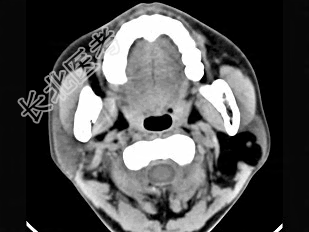

- 单项选择题女性50岁,左侧面部肿胀, CT检查如图,应考虑为 ( )

A、左侧腮腺囊腺瘤

B、左侧腮腺囊肿

C、左侧腮腺脂肪瘤

D、左侧腮腺错构瘤

E、左侧腮腺炎